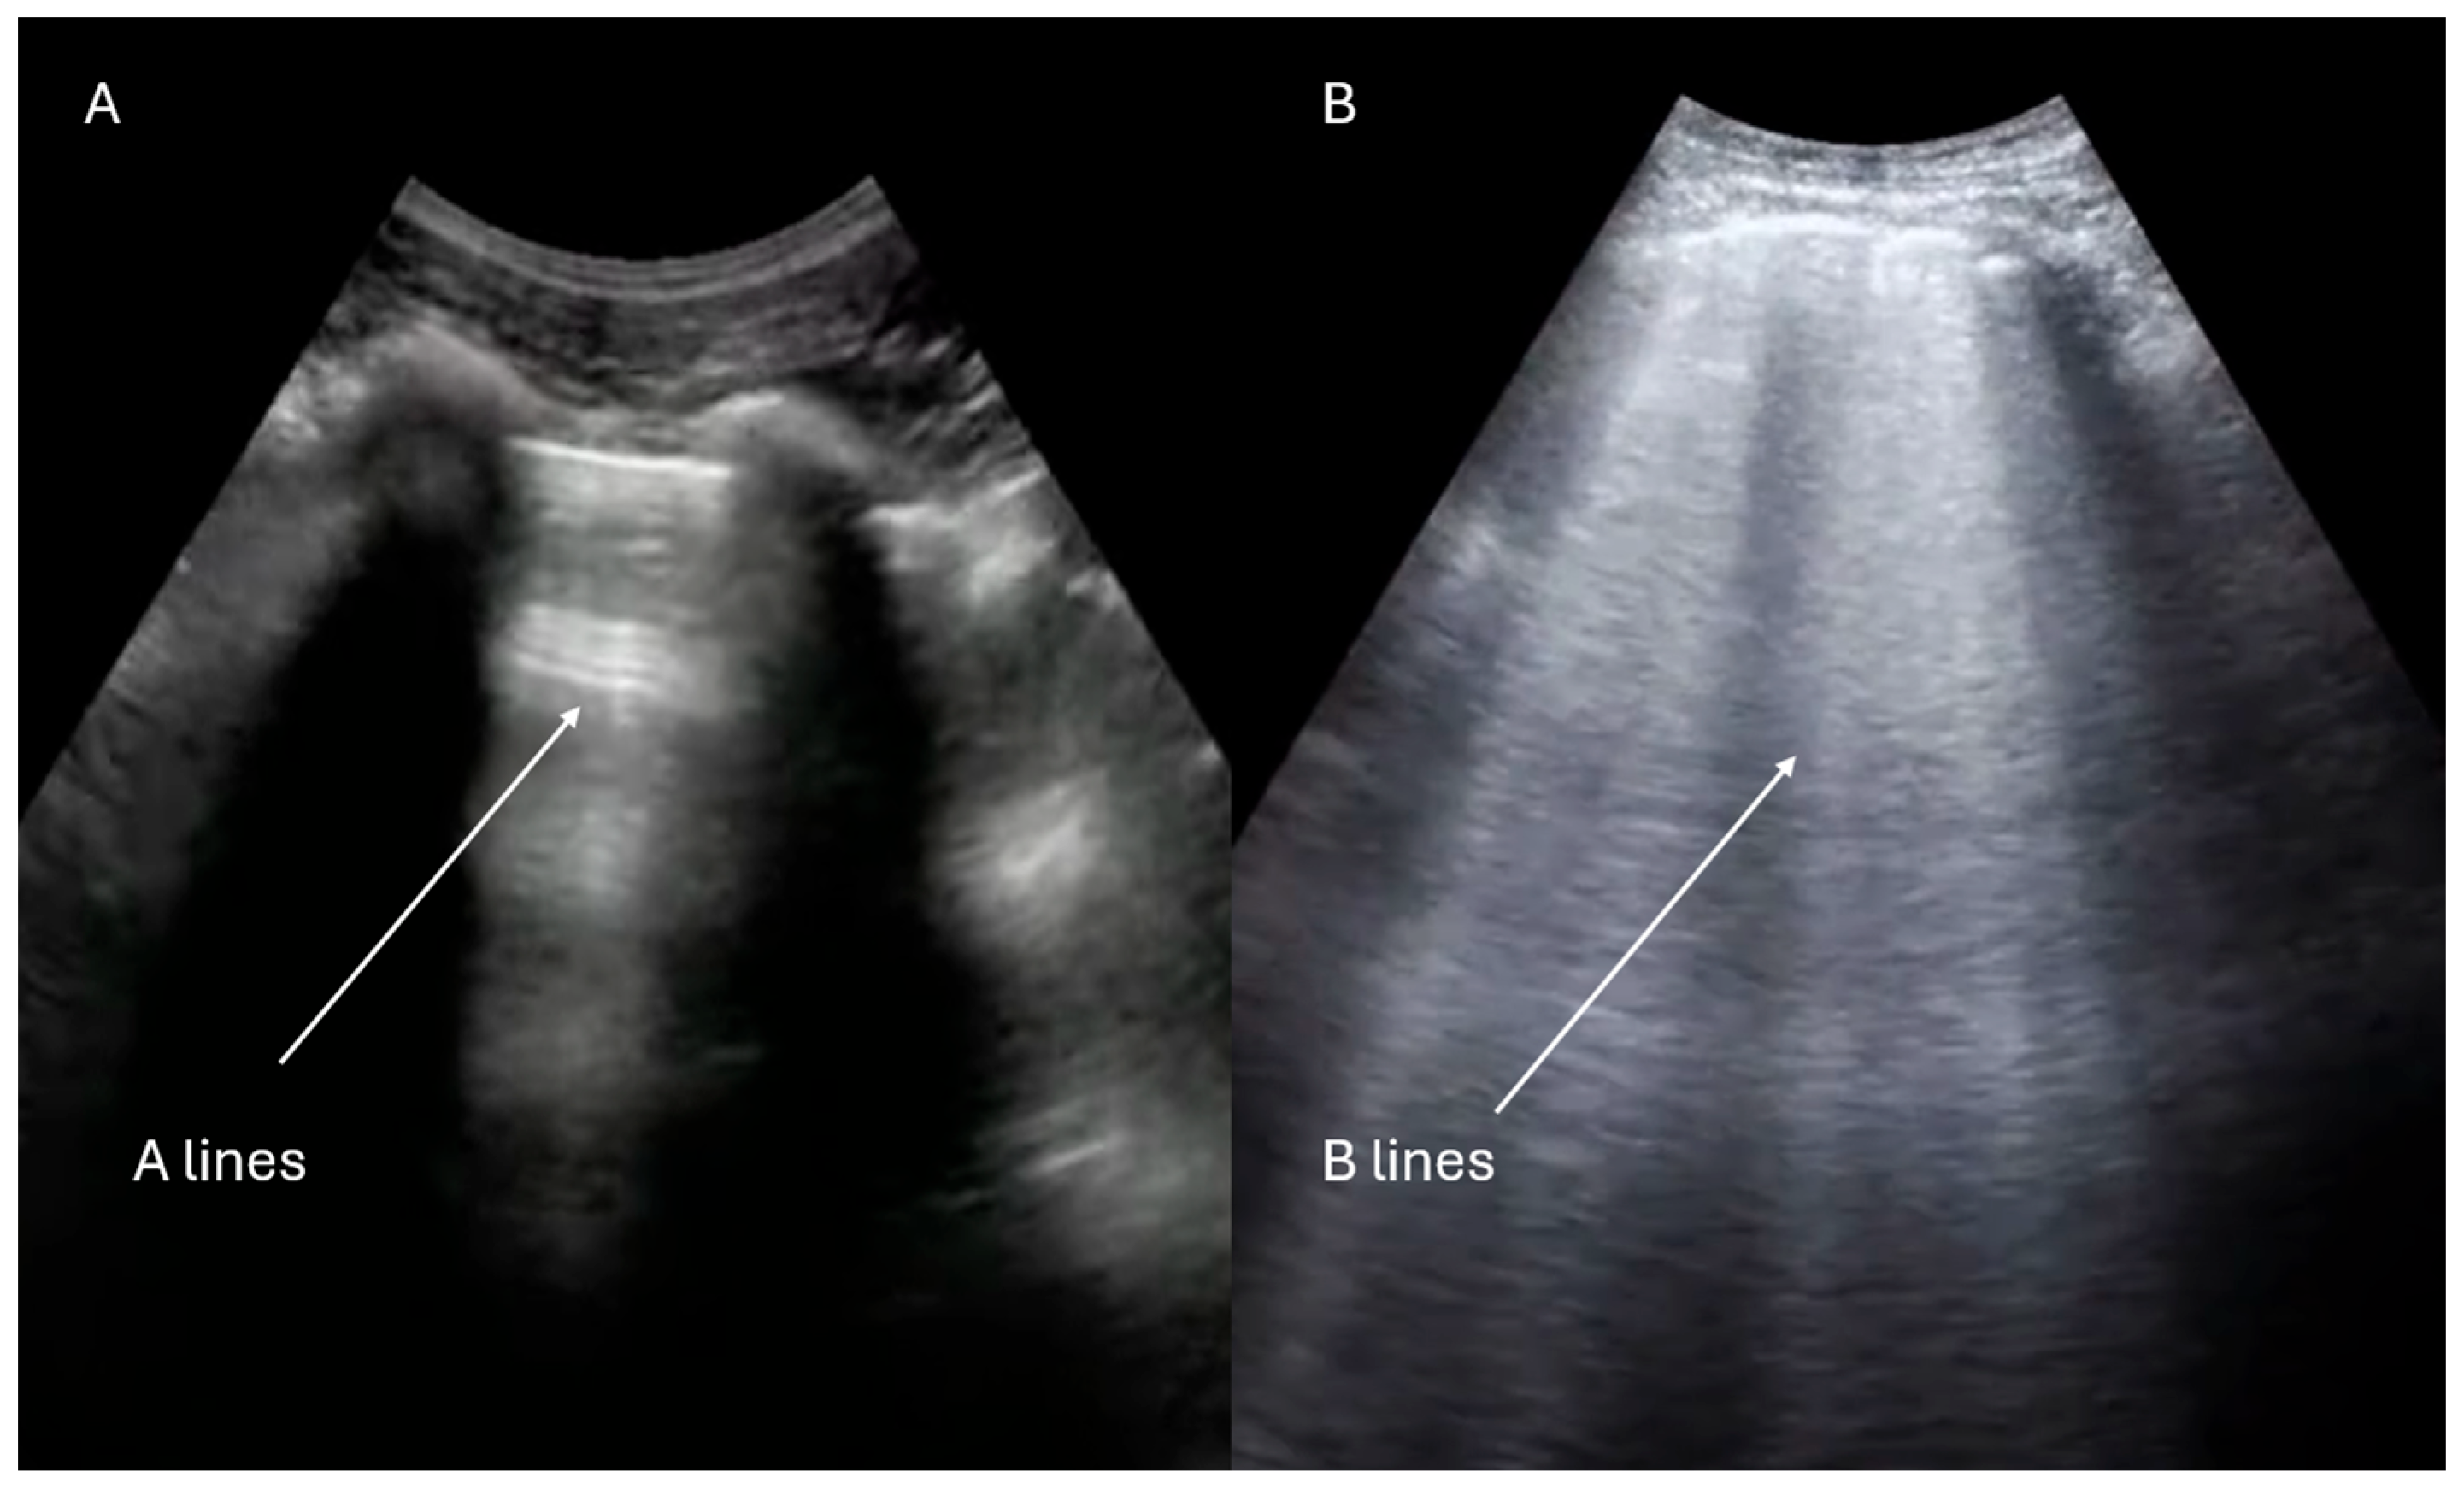

- Lichtenstein, D.A. Lung ultrasound in the critically ill. Ann. Intensive Care 2014, 4, 1. [Google Scholar] [CrossRef] [PubMed]

- Lichtenstein, D.A.; Mezière, G.A. Relevance of lung ultrasound in the diagnosis of acute respiratory failure: The BLUE protocol. Chest 2008, 134, 117–125. [Google Scholar] [CrossRef]

- Volpicelli, G.; Elbarbary, M.; Blaivas, M.; Lichtenstein, D.A.; Mathis, G.; Kirkpatrick, A.W.; Melniker, L.; Gargani, L.; Noble, V.E.; Via, G.; et al. International Liaison Committee on Lung Ultrasound (ILC-LUS) for International Consensus Conference on Lung Ultrasound (ICC-LUS). International evidence-based recommendations for point-of-care lung ultrasound. Intensive Care Med. 2012, 38, 577–591. [Google Scholar] [CrossRef]

| Lung ultrasound adjunct (B-lines, effusions, PTX signs) | Yes (integrated FoCUS) | Yes (integrated FoCUS) | Optional adjunct |